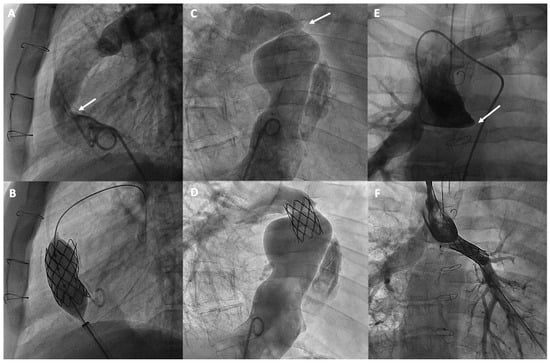

| Fontan Pathway Obstructions | Balloon angioplasty, and especially stenting, are commonly used to treat obstructions in the Fontan pathway and pulmonary branch stenosis. |

| Fenestrations | Fenestration can be created by puncture, usually with subsequent stent implantation, or more commonly, closed percutaneously using transcatheter occlusion devices. |

| Ventriculo-pulmonary Communication | Residual antegrade connections between the ventricle and pulmonary circulation can be closed percutaneously using occlusion devices. |